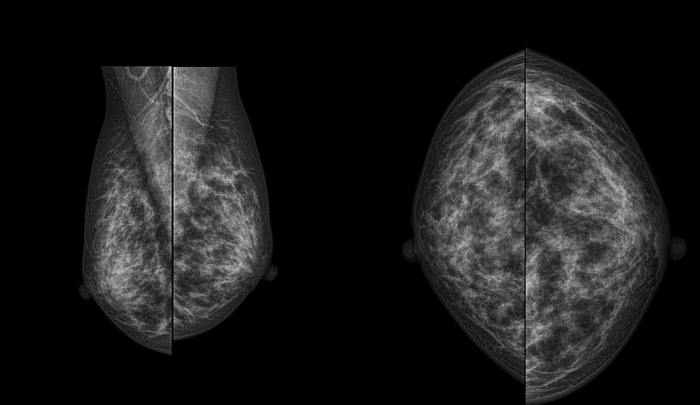

Маммография – это тип специального медицинского обследования, которое проводится с применением системы рентгена с малыми дозами облучения для исследования груди женщины (и мужчины - по показаниям).

Аппарат, на котором врач проводит данное исследование, называется — маммограф. Исследование на нем позволяет выявить болезни молочных желез на ранних стадиях, в том числе и такие опасные, как рак молочных желез.

Исследование проводится стоя, предварительно сняв верхнюю и нижнюю одежду области исследования, а также все украшения в области зоны интереса. Для получения четких и подробных снимков, молочную железу располагают между двух пластин маммографа, которые слегка сдавливая, фиксируют ее в неподвижном положении, добиваясь равномерного распределения тканей. Затем специалист делает снимок молочной железы в боковой и прямой проекции. Исследуются поочередно обе груди.